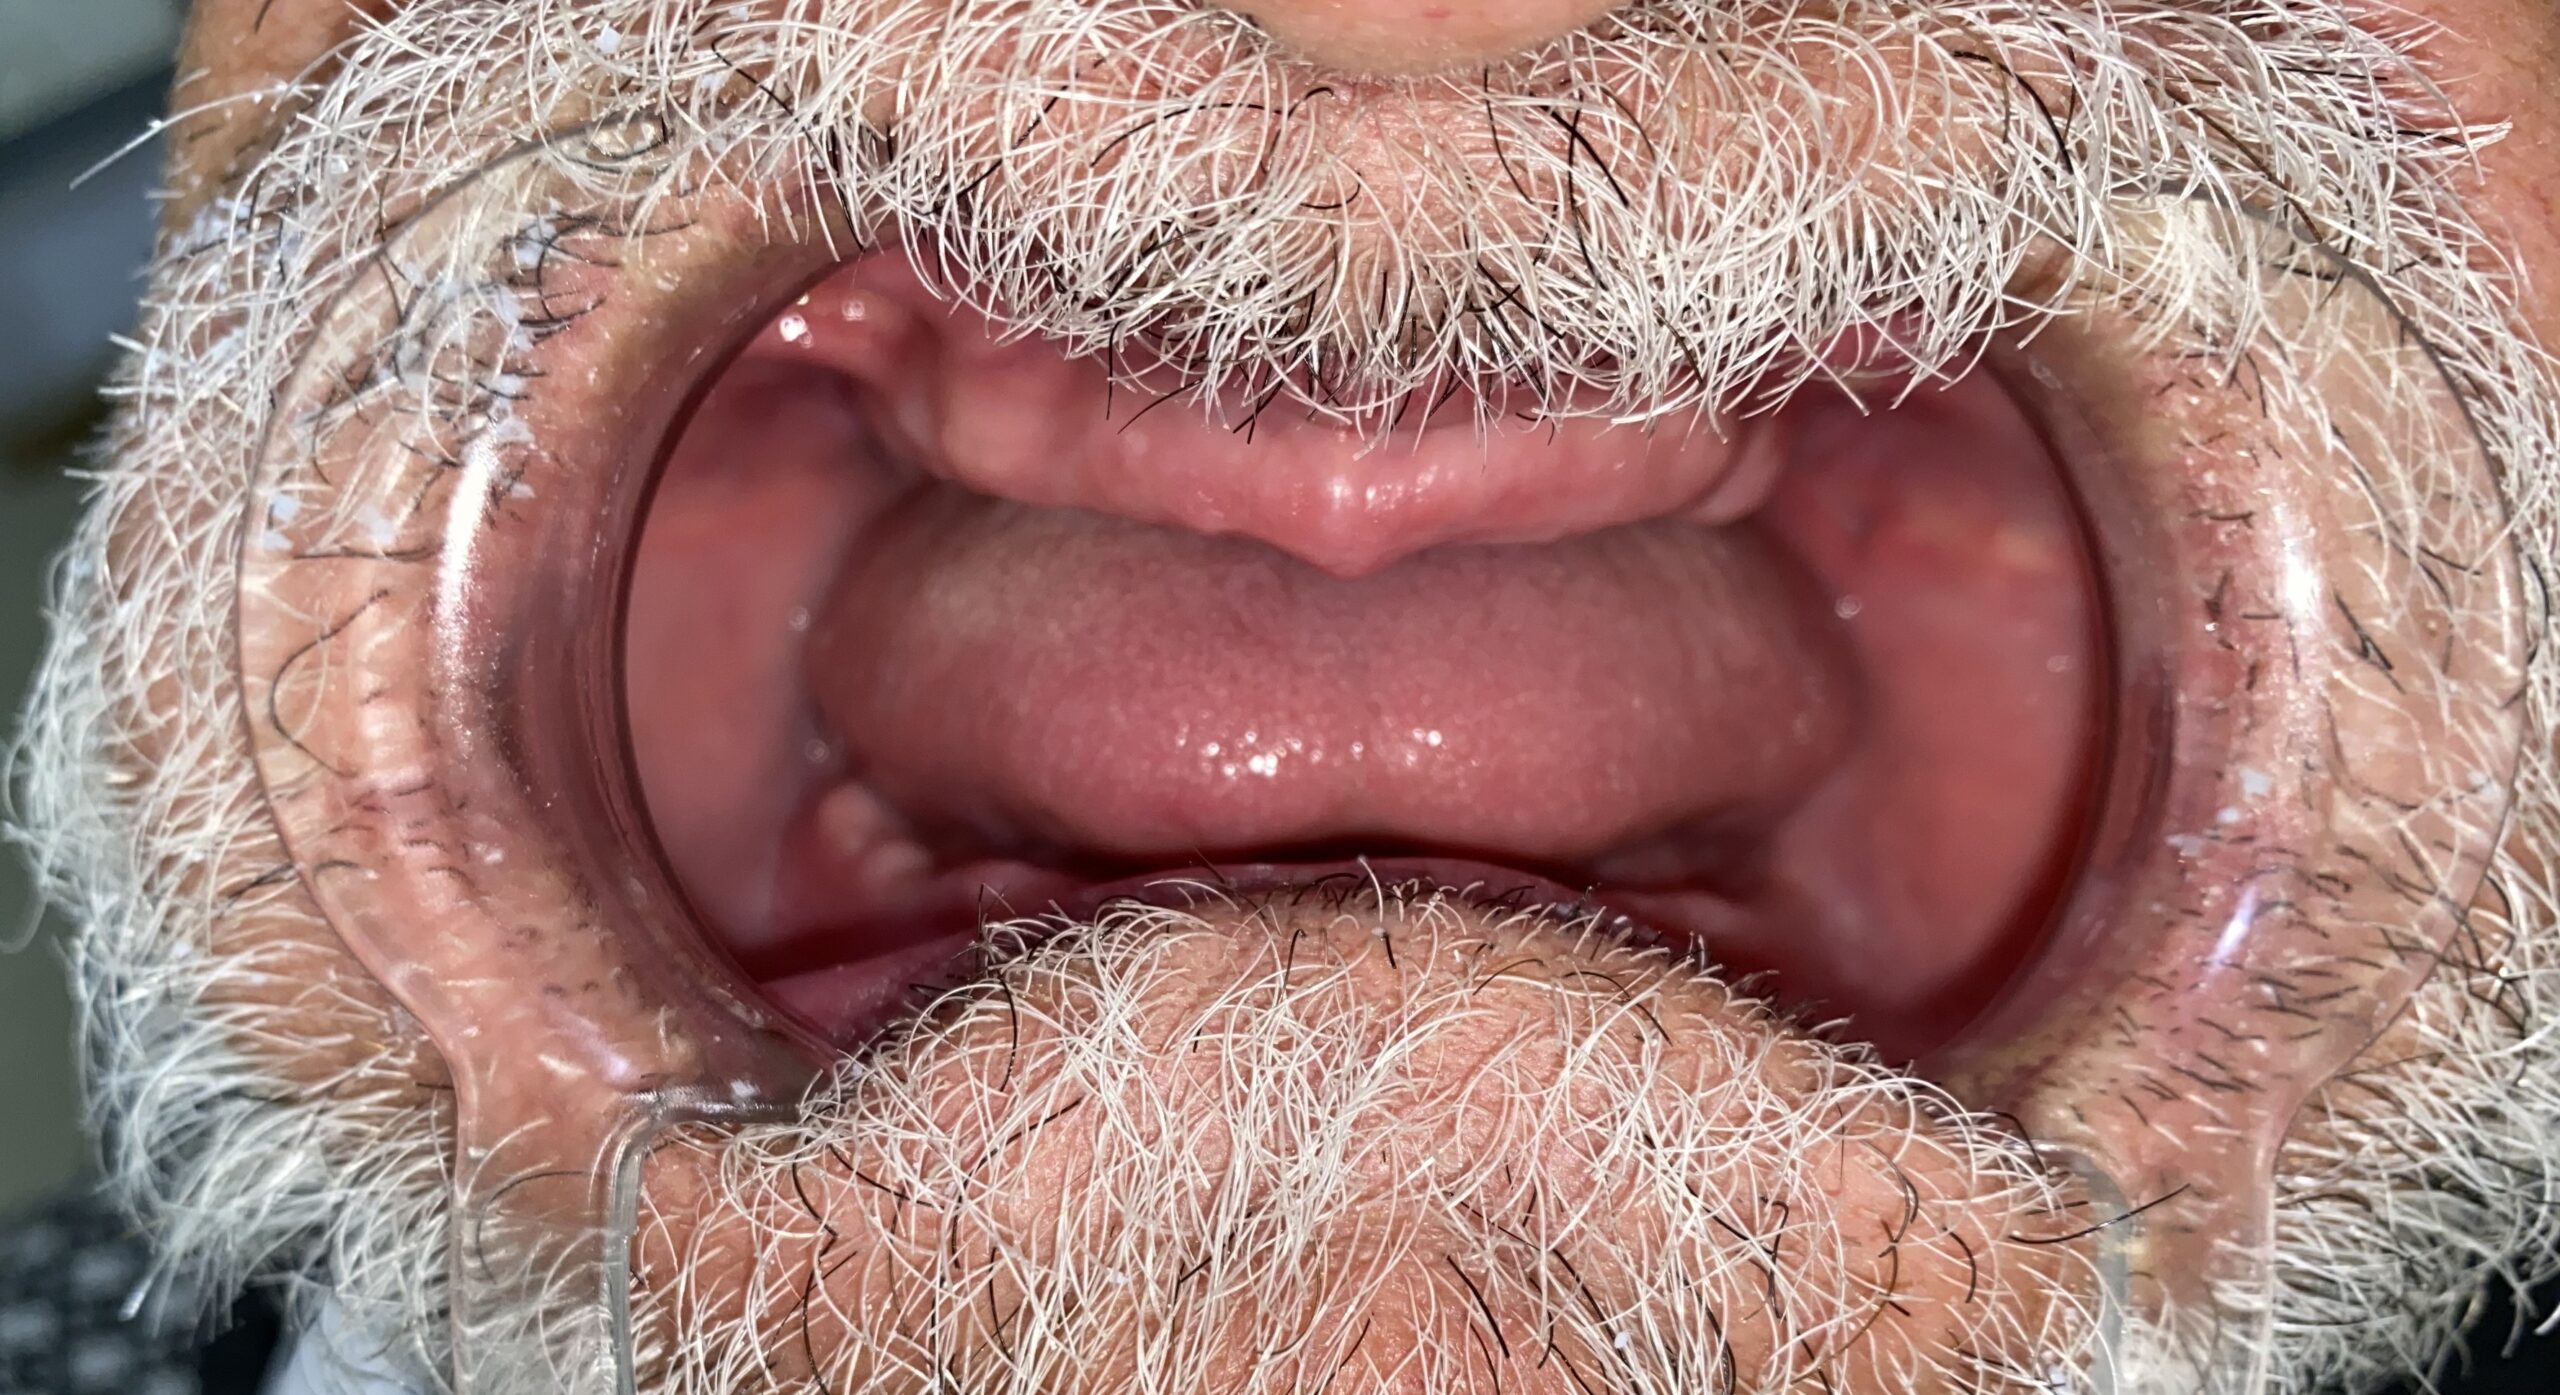

کاشت ایمپلنت و نصب پوش

قبل و بعد بازسازی کامل با ایمپلنت

قبل و بعد لیمینت و ایمپلنت